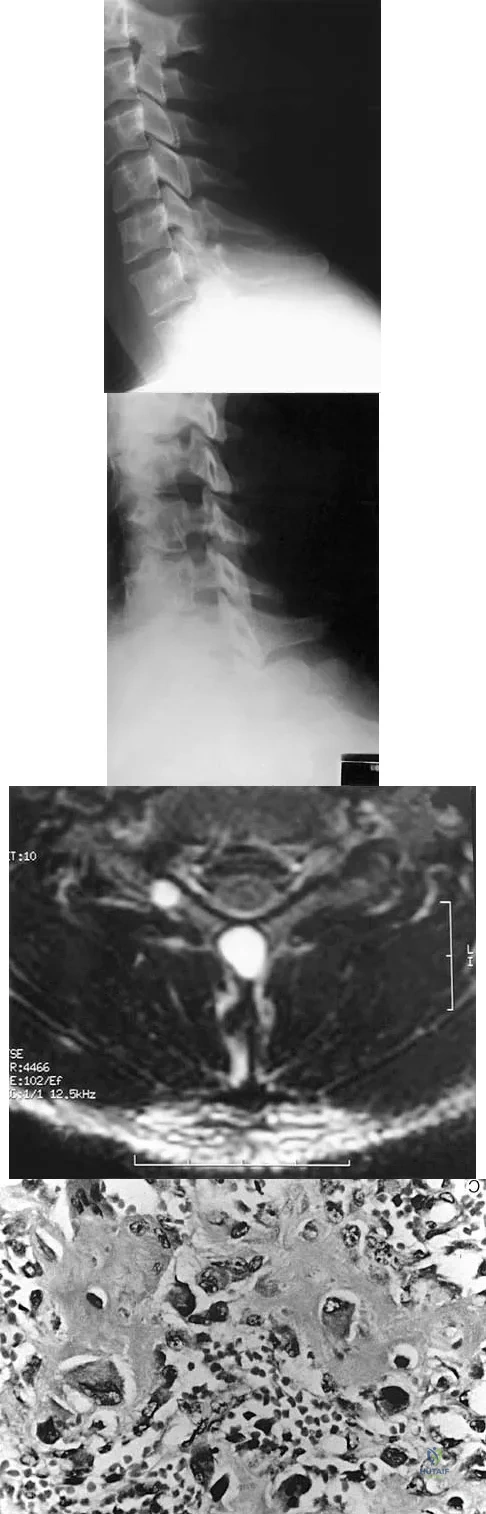

A 13-year-old girl has had increasing left hip pain for the past 4 months. A radiograph, bone scan, MRI scan, and photomicrograph are shown in Figures 1a through 1d. Which of the following immunohistochemistry results would confirm the most likely diagnosis?

Explanation